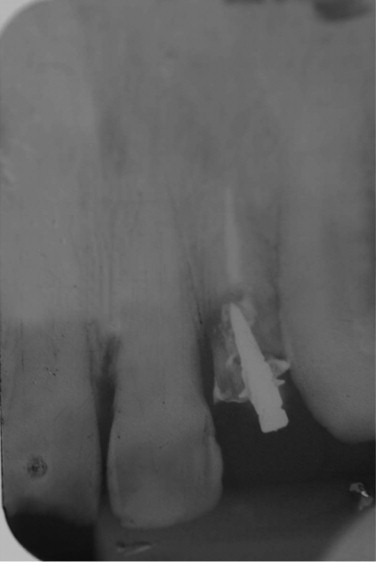

A 57-year-old patient came to the Department of Dental Material and Prosthodontics of the Aracatuba Dental School, complaining of a fracture of the dental element 22 (Fig. 1). This element was previously restored with a single partial fixed prosthesis with a metallic core. The patient presented good general health. The clinical exam indicated a lack of gingival smile, a class IV fracture at the incisal portion of the 11 and a vertical root fracture of the 22. Due to this fracture, tooth extraction was indicated. The patient assigned an informed consent for proposed oral rehabilitation.

Fig. 1.

Initial radiograph.